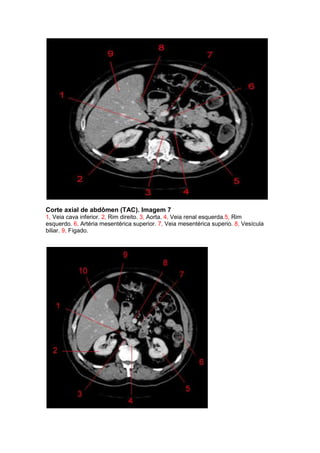

Corte axial de abdômen (TAC). Imagem 7

1, Veia cava inferior. 2, Rim direito. 3, Aorta. 4, Veia renal esquerda.5, Rim

esquerdo. 6, Artéria mesentérica superior. 7, Veia mesentérica superio. 8, Vesícula

biliar. 9, Fígado.

Corte axial de abdômen (TAC). Imagem 8

1, Veia cava inferior. 2, Rim direito. 3, Origem da artéria renal direita.4, Aorta. 5, Rim

esquerdo. 6, Cólon descendente. 7, Artéria mesentérica superior. 8, Veia mesentérica

superio. 9, Vesícula biliar.10, Fígado.

Corte axial deabdômen (TAC). Imagem 7 1, Veia cava inferior. 2, Rim direito. 3, Aorta. 4, Veia renal esquerda.5, Rim esquerdo. 6, Artéria mesentérica superior. 7, Veia mesentérica superio. 8, Vesícula biliar. 9, Fígado.

Corte axial deabdômen (TAC). Imagem 8 1, Veia cava inferior. 2, Rim direito. 3, Origem da artéria renal direita.4, Aorta. 5, Rim esquerdo. 6, Cólon descendente. 7, Artéria mesentérica superior. 8, Veia mesentérica superio. 9, Vesícula biliar.10, Fígado. Corte axial de abdômen (TAC). Imagem 9 1, Veia cava inferior. 2, Rim direito. 3, Aorta. 4, Rim esquerdo. 5,Cólon descendente. 6, Artéria mesentérica superior. 7, Veia mesentérica superio. 8, Vesícula biliar. 9, Fígado.